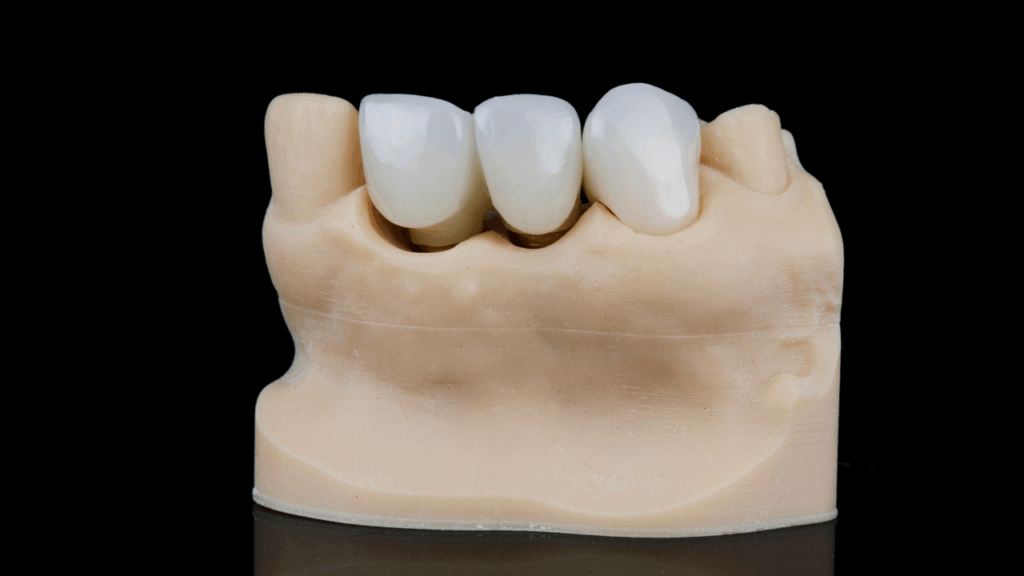

Korona stomatologiczna to stałe uzupełnienie protetyczne, które zakłada się na oszlifowany ząb lub implant. Jej głównym zadaniem jest odtworzenie naturalnego kształtu, koloru i funkcji zęba, a także ochrona przed dalszym uszkodzeniem.

Warto odróżnić pojęcie korony protetycznej od naturalnej korony zęba. Naturalna korona to ta część zęba, którą widzimy nad dziąsłem. Natomiast korona protetyczna to swego rodzaju „nakładka” – sztuczna osłona, idealnie dopasowana do reszty uzębienia.

- Korony pełnoceramiczne – bardzo estetyczne, polecane do przednich zębów, niemal nie do odróżnienia od naturalnych.

- Korony porcelanowe na metalu – łączą trwałość z dobrą estetyką, popularne i stosunkowo przystępne cenowo.

- Korony cyrkonowe – niezwykle wytrzymałe i estetyczne, odporne na przebarwienia.

Wykonanie korony w laboratorium protetycznym

- Technik dentystyczny przygotowuje koronę zgodnie z projektem, dbając o estetykę i dopasowanie.